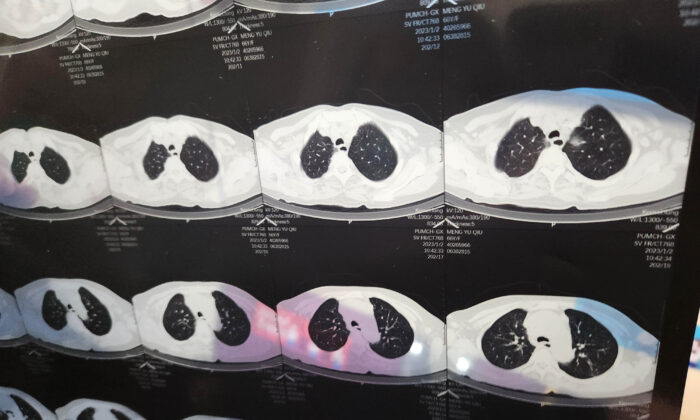

A doctor looks at a CT image of a patient in Haidian, Beijing, China, on Jan 2, 2023. (CFOTO/Future Publishing via Getty Images)

Only after a series of X-ray scans at the hospital did the family realize the gravity of the situation: His lungs appeared mostly white. Healthy lungs, by contrast, would normally appear as dark regions in an X-ray or CT scan.

“White lung,” once a little-known phrase, has been a top trending word on Chinese social media amid an expansive COVID outbreak sweeping China, before censors swooped in to scrub discussion of the phenomenon. The white patches indicate areas of inflammation, which causes excessive fluid accumulation in the lungs.